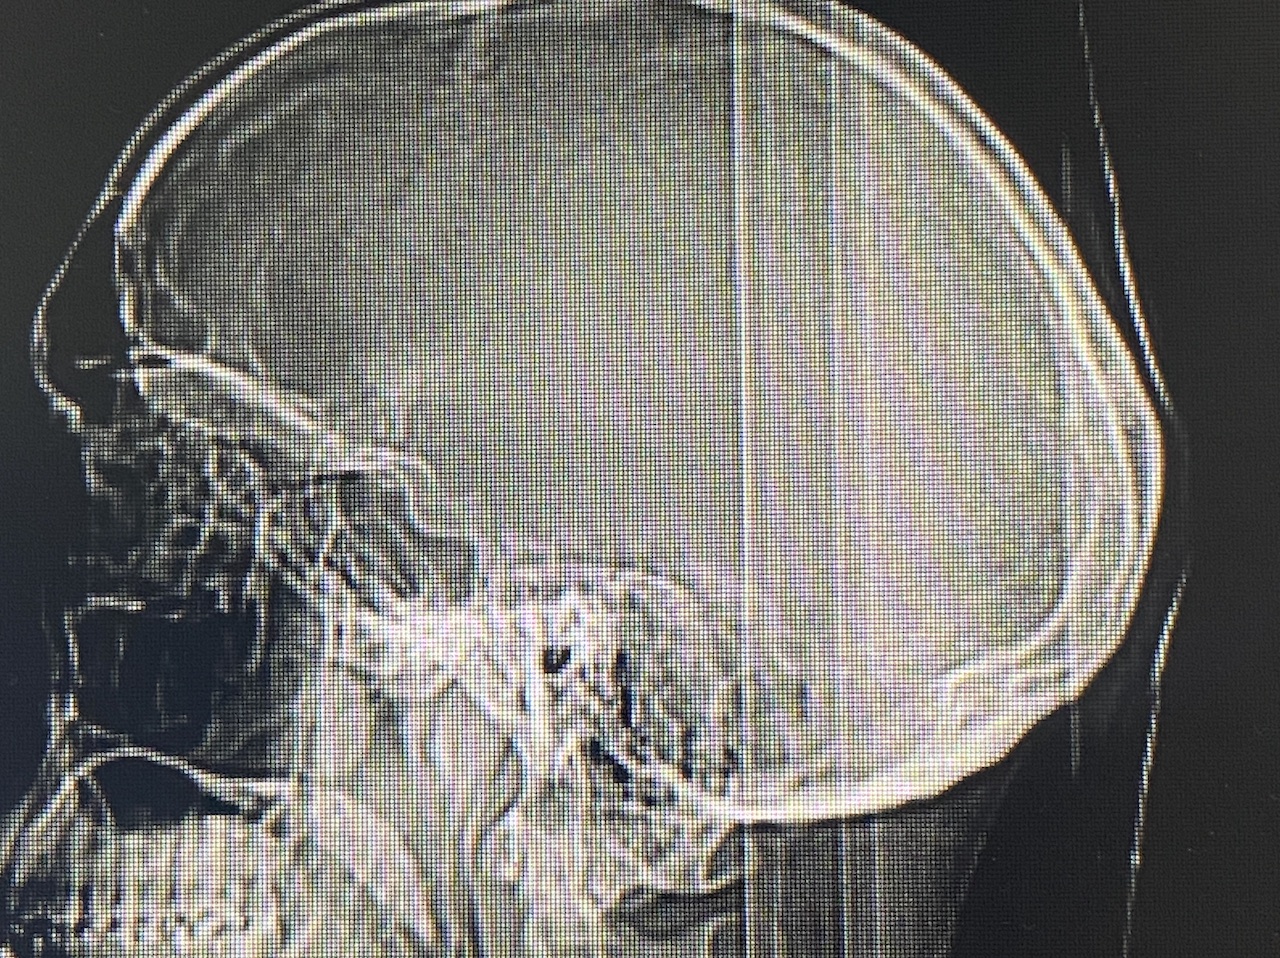

Severe narrowing skull deformity from prior sagittal craniosynostosis repair as an adult.

Complete replacement of entire skull by a custom implant with temporal fat injections.